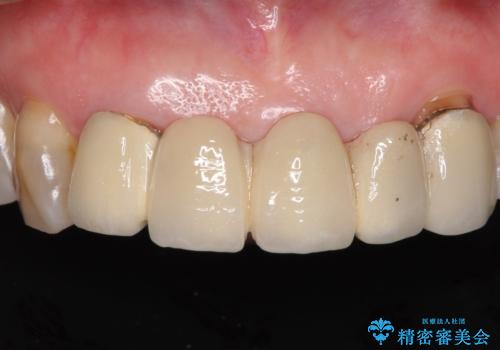

- アンバランスな色や形、歯肉ラインの黒い縁が目立ってしまったブリッジの作り直しを希望して来院された患者様です。

自然な仕上がりとするため、金属を使用しないオールセラミックブリッジにより補綴治療を行うこととしました。

装着されていたブリッジは、支台となっている歯と欠損している歯で色が大きく異なっていましたが、オールセラミックとしたことで、全体的に色調の整った仕上がりとなりました。

歯肉ラインがきれいに整い、患者様には大変満足していただきました。